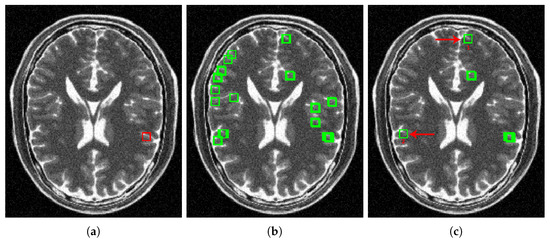

4.2.2. Real Data